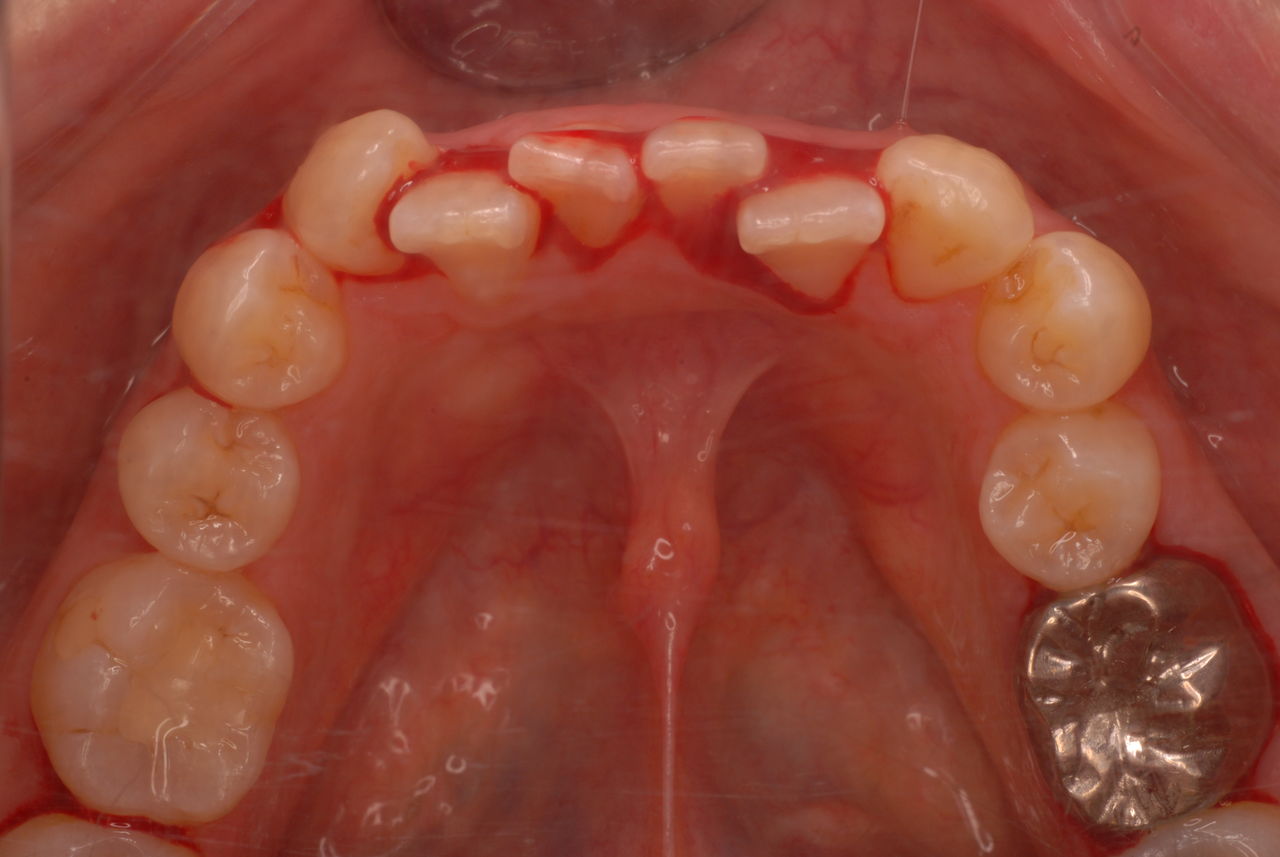

隣の14歳大臼歯がひどい虫歯になり治療不可能になりつつある状態のレントゲン

親知らずを取ることを嫌がる方が多いのですが、もし親知らずとその隣の14歳大臼歯の間に虫歯ができたり歯周病を罹患した場合、どれほど治療が大変で再発も起こりやすいか理解できない方がおおいのです。